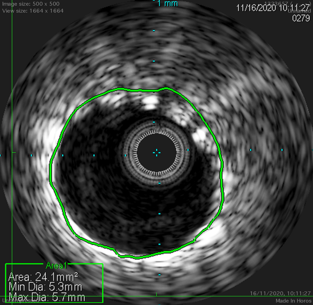

使用Sterling球囊预扩张后植入Eluvia DES的病例。IVUS评估显示,支架植入后管腔获得显著,但在支架局部不规整处最小径仅为3.7mm,提示局部扩张可能不充分。

图:支架形态规则处,有效面积24.1mm2,最小径 5.3mm,最大径 5.7mm。